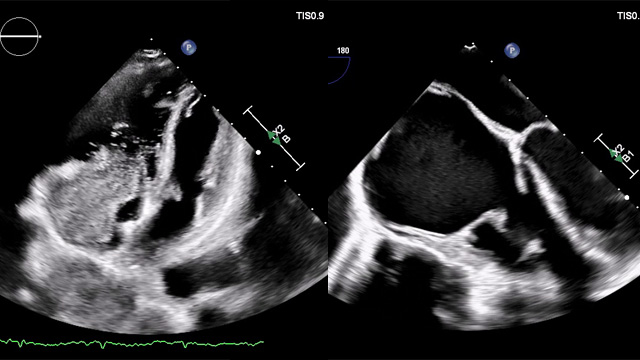

How should I manage a patient with insufficient surgical closure of the left atrial appendage

Incomplete surgical LAA closure: how would you proceed?

Despite prior closure with an Atriclip during CABG, transoesophageal echocardiography reveals a persistent LAA gap in a high-risk patient with recurrent bleeding.

Explore the clinical details, imaging, and treatment dilemmas—then share your management approach!